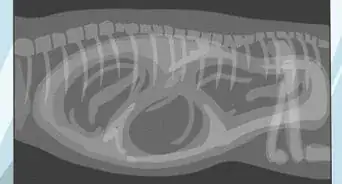

2Stand back and assess your dog overall. Watch how the dog is standing or sitting. Does it look comfortable and relaxed, or does it have difficulty getting up or down? Watch the dog's breathing and count the number of breaths it takes a minute at rest. Normal is 20 - 30 a minute.[7]

- At a regular room temperature, not in excessive heat when the dog is panting to cool off, its breathing should be unhurried and difficult to see. Exaggerated breathing movements, especially when the dog uses its stomach muscles to haul air in and out of its lungs is a sign of breathing difficulty and should be checked out.[8]